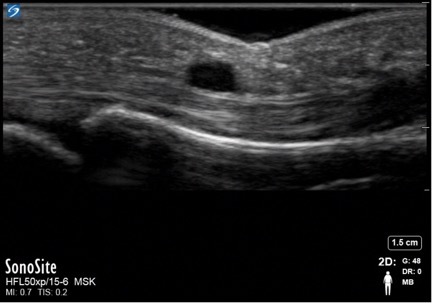

Hand Cyst 2 Image